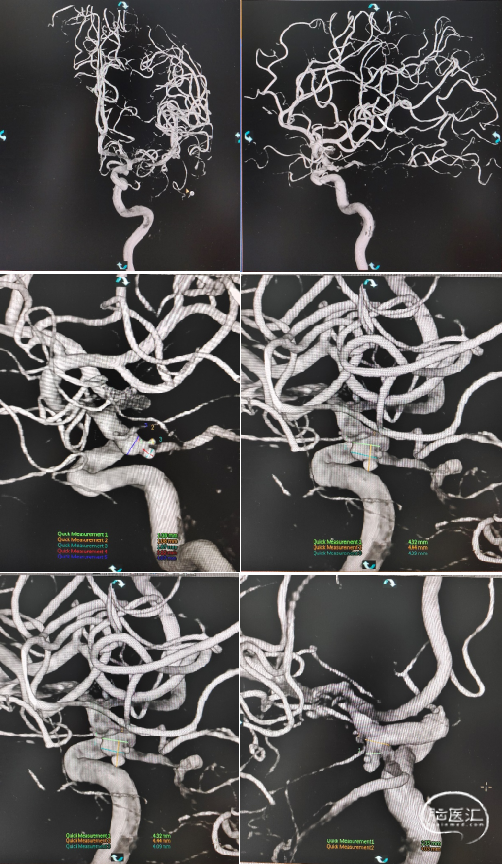

造影所见:双侧颈动脉血管稍迂曲僵硬,双侧后交通动脉开放,左侧颈内动脉后交通段可见一“囊状”突起,大小约6.19mm*4.07mm*2.35mm,瘤颈4.03mm,基底宽,边缘不光整,有两个子瘤,指向后下方,后交通动脉从瘤颈处发出。

3D

患者平卧位,双管喉罩全麻,术野常规消毒铺无菌巾,以Seldinger氏技术穿刺右股动脉置8F鞘,肝素盐水(5000U/500ML)持续滴注置入8F输送导管+6F远端通路导管,输送导管于左侧颈内动脉起始端,远端通路导管置于左侧颈内动脉海绵窦段,接驳Y阀,肝素盐水(5000U/500ML)持续滴注,手推造影剂,获得理想的工作角度,充分暴露动脉瘤瘤体、瘤颈、载瘤动脉、后交通动脉以及远端通路导管头端,通过在微导丝引导下用一根微导管置于左侧大脑中动脉内。

通过在微导丝引导下用一根微导管置于动脉瘤瘤体,选择一枚凤弹簧圈(AEC-2.5-06-S)由微导管置入瘤囊下方子瘤内,微导管(150cm*6cm)内送入支架(Neuroform Atlas 4.0mm*21mm),释放支架,支架头端位于左侧大脑中动脉M1段内,末端位于左侧颈内动脉眼段,支架展开贴壁满意,撤出微导管(150cm*6cm)。微导管内继续送入一枚凤弹簧圈(AEC-04-10-S)“成栏”,“成篮”满意,依次置入凤弹簧圈2枚(AEC-2.5-04-H,AEC-02-02-S)。